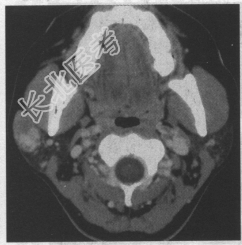

- 单项选择题患者,女, 30岁。无意中发现右侧面部包块半年余。CT检查如下图,诊断为

A、腮腺混合瘤

B、腮腺淋巴瘤

C、腮腺神经鞘瘤

D、腮腺畸胎瘤

E、腮腺囊肿